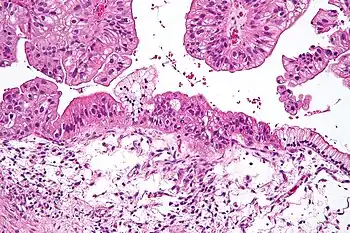

Micrograph of a mucinous ovarian carcinoma stained by H&E

Mucinous

Mucinous tumors include mucinous adenocarcinoma and mucinous cystadenocarcinoma.[29]

Mucinous adenocarcinoma

Mucinous adenocarcinomas make up 5–10% of epithelial ovarian cancers. Histologically, they are similar to intestinal or cervical adenocarcinomas and are often actually metastases of appendiceal or colon cancers. Advanced mucinous adenocarcinomas have a poor prognosis, generally worse than serous tumors, and are often resistant to platinum chemotherapy, though they are rare.[29]